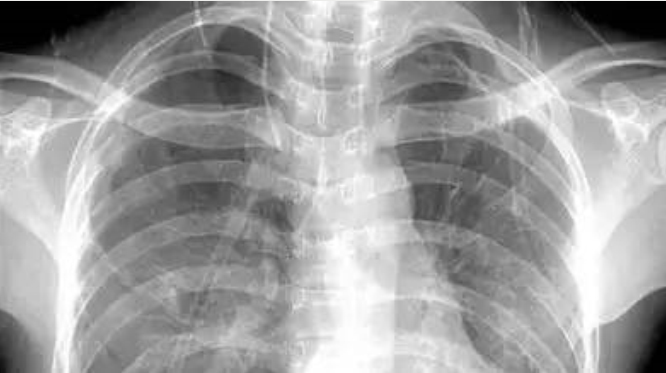

3〠胸部——粗看X线片,细看CT,看肺尽é‡ä¸è¦é€‰æ ¸ç£ï¼ˆå 使€§ç—…å˜çœ‹å¼¥æ•£æ˜¯å¦å—é™é™¤å¤–)

X线胸片å¯ç²—略检查心è„ã€ä¸»åŠ¨è„‰ã€è‚ºã€èƒ¸è†œã€è‚‹éª¨ç‰ï¼Œå¯ä»¥æ£€æŸ¥æœ‰æ— 肺纹ç†å¢žå¤šã€è‚ºéƒ¨é’™åŒ–点ã€ä¸»åŠ¨è„‰ç»“é’™åŒ–ç‰ã€‚

胸部CTæ£€æŸ¥æ˜¾ç¤ºå‡ºçš„ç»“æž„æ›´æ¸…æ™°ï¼Œå¯¹èƒ¸éƒ¨ç—…å˜æ£€å‡ºæ•感性和显示病å˜çš„准确性å‡ä¼˜äºŽå¸¸è§„X线胸片,特别是对于早期肺癌确诊有决定性æ„义。但是CT检查的è¾å°„剂é‡é«˜äºŽXçº¿ã€‚æ ¸ç£å¯¹äºŽè‚ºéƒ¨ç–¾ç—…的诊æ–,应用éžå¸¸æœ‰é™ã€‚